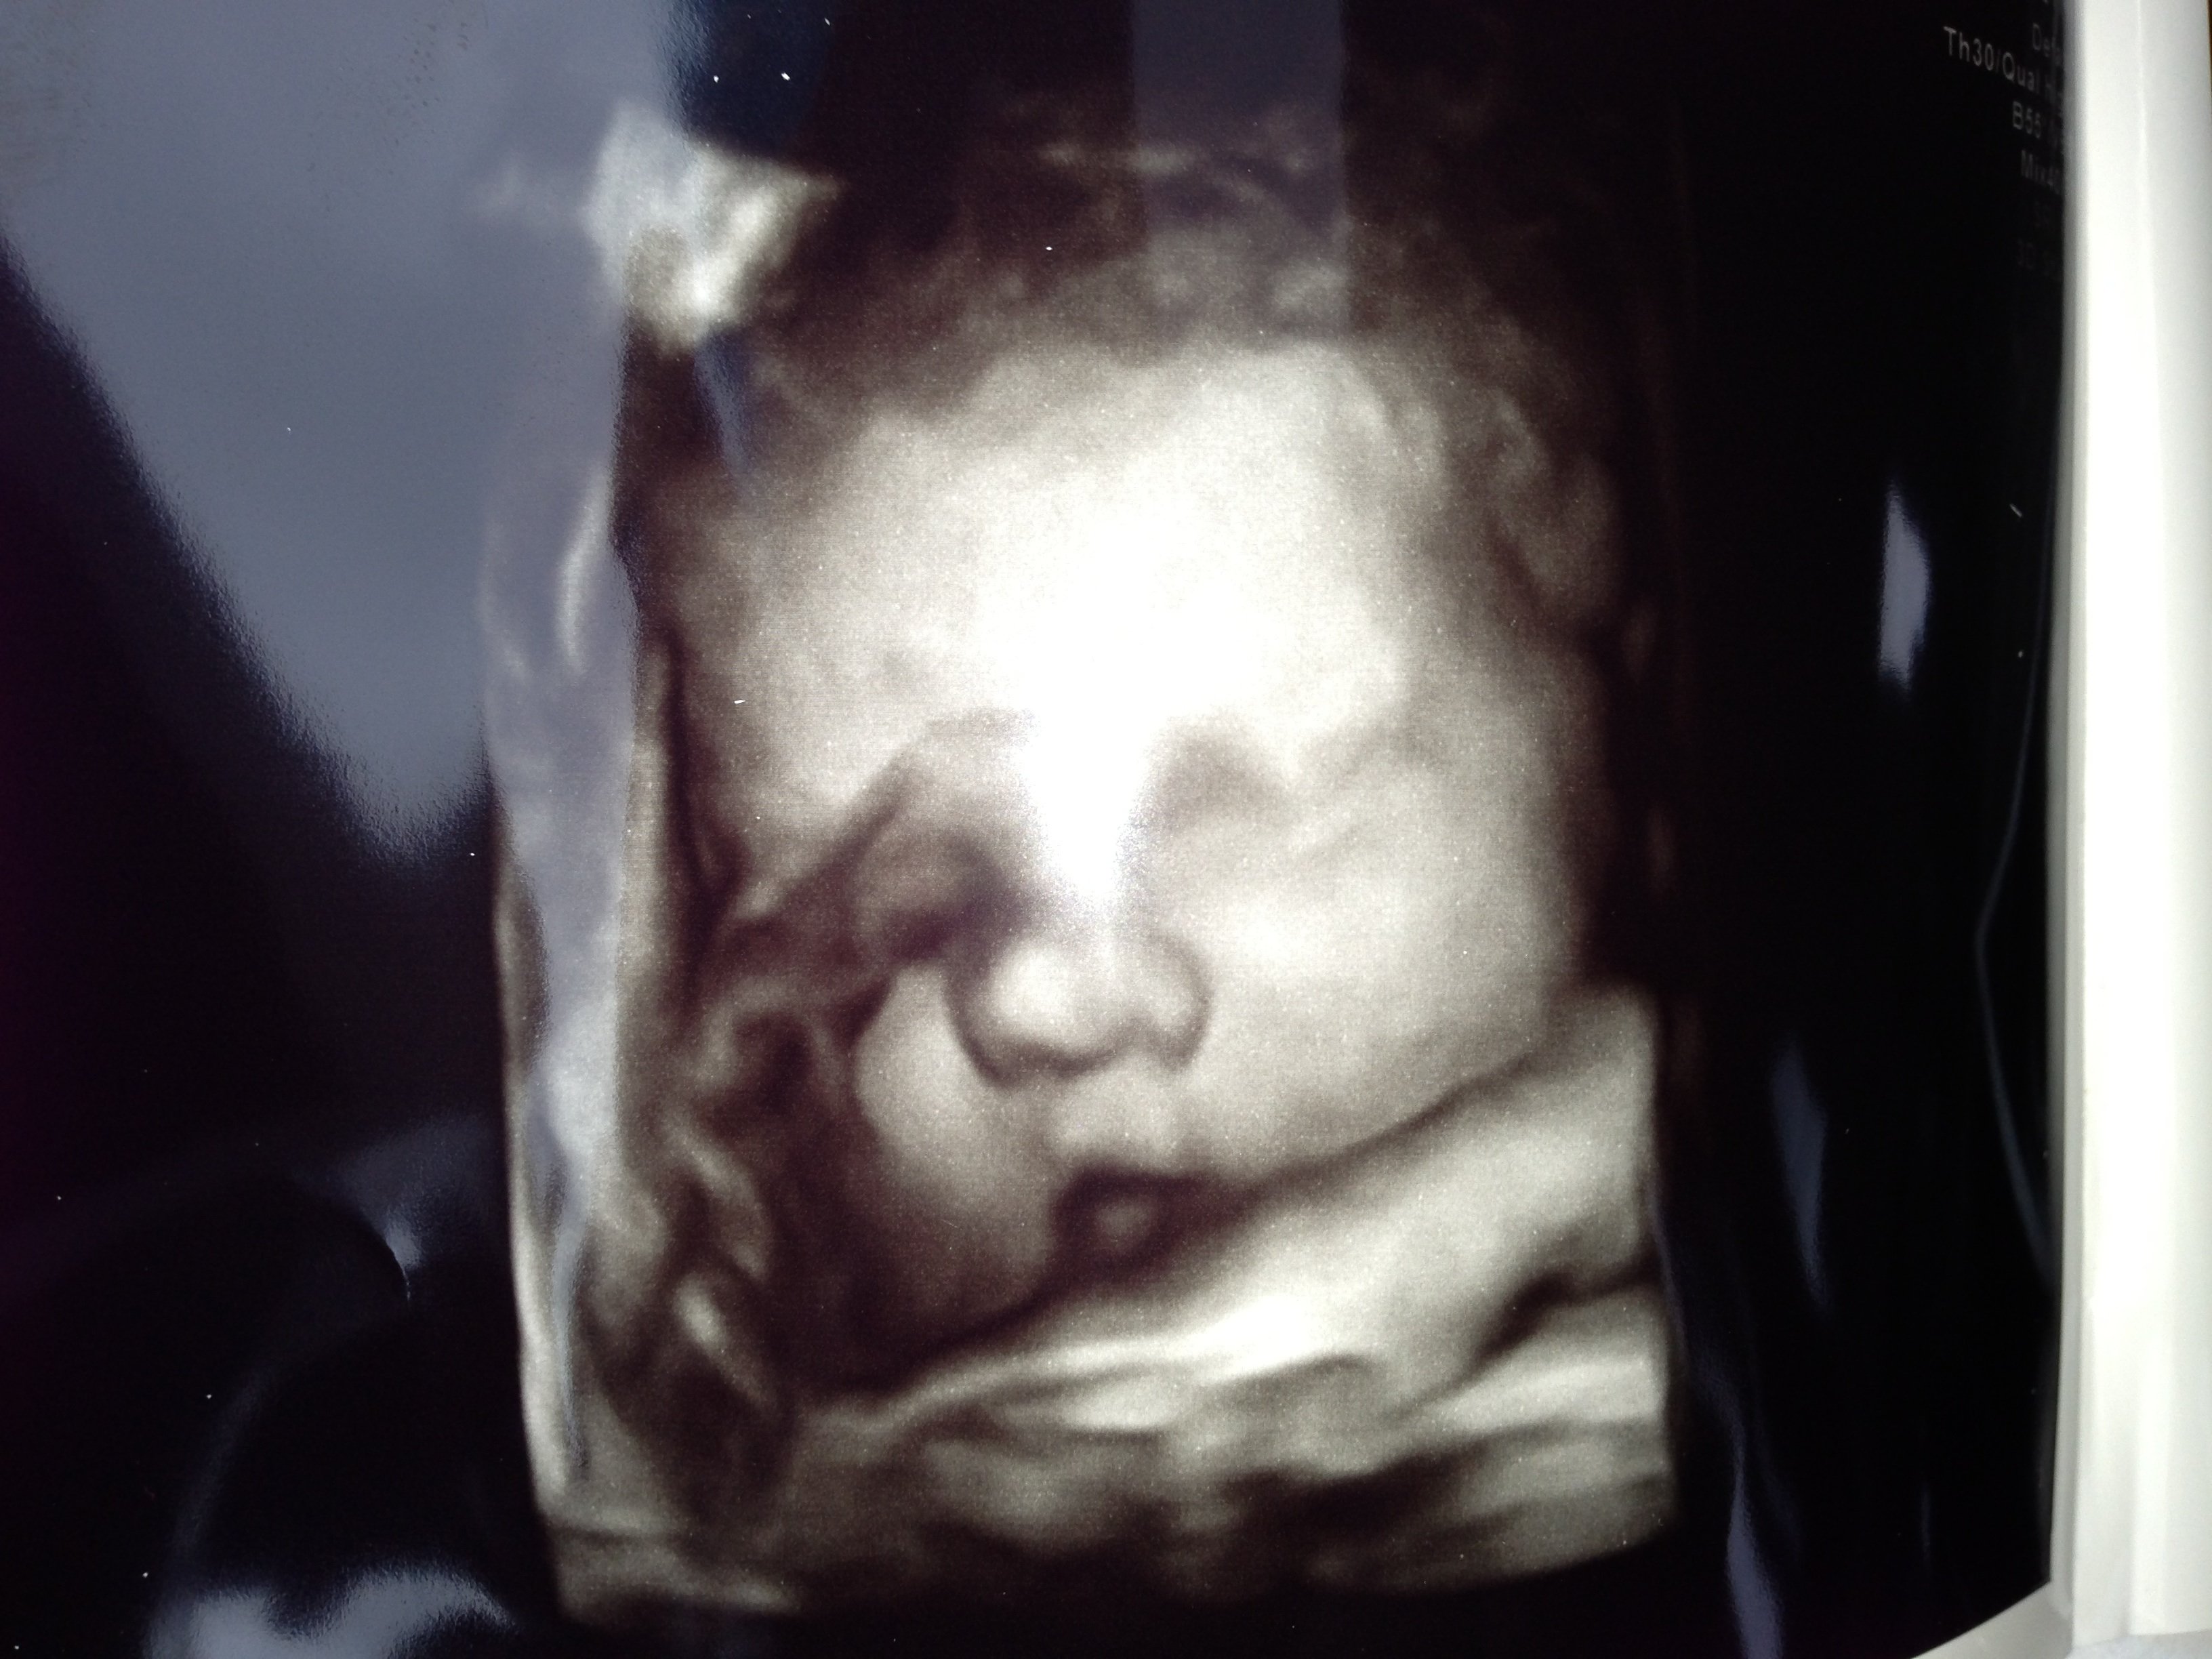

Re: first PIP attempt...

Patiently waiting for little brother!